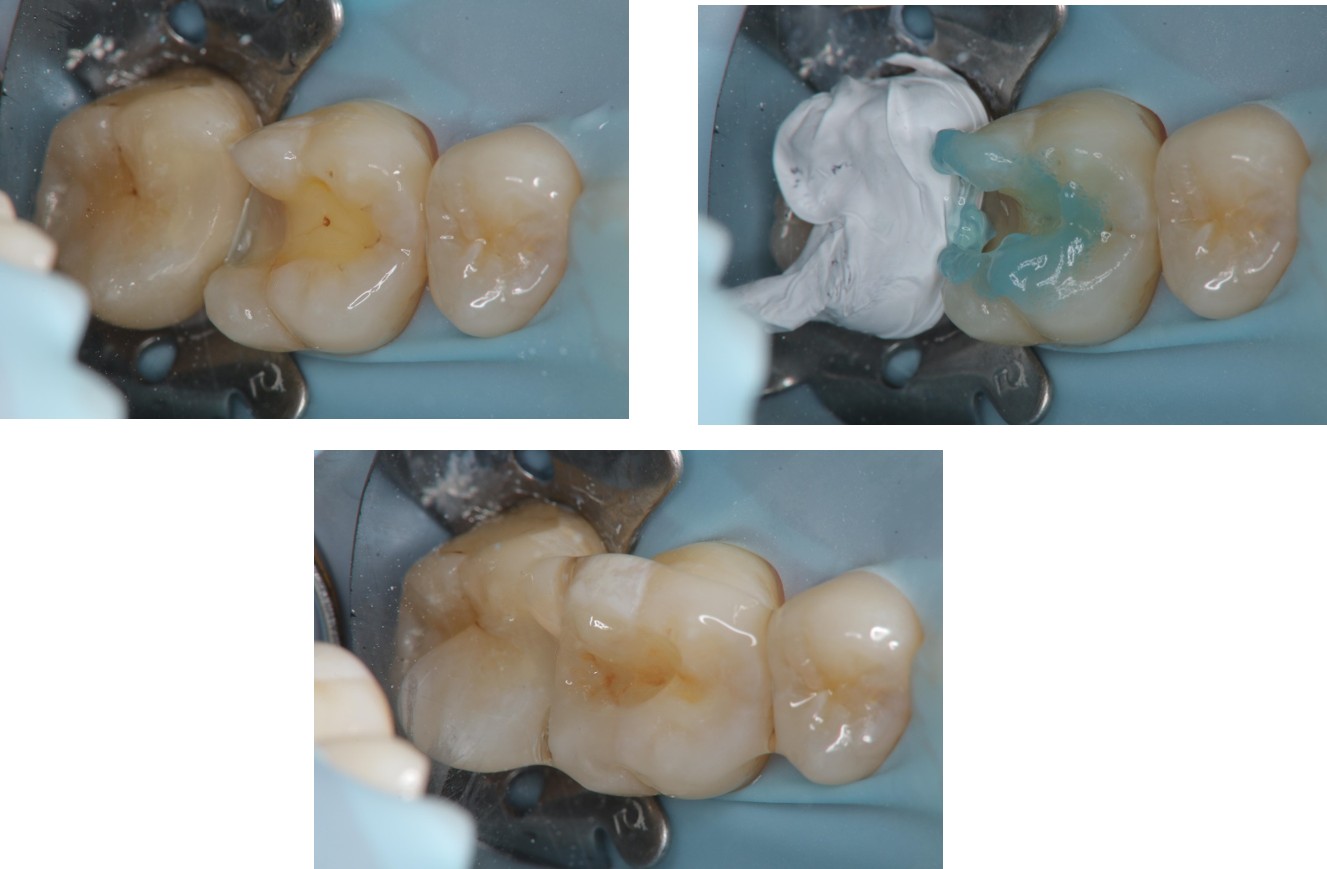

上橡皮障,隔水,黏著瓷塊